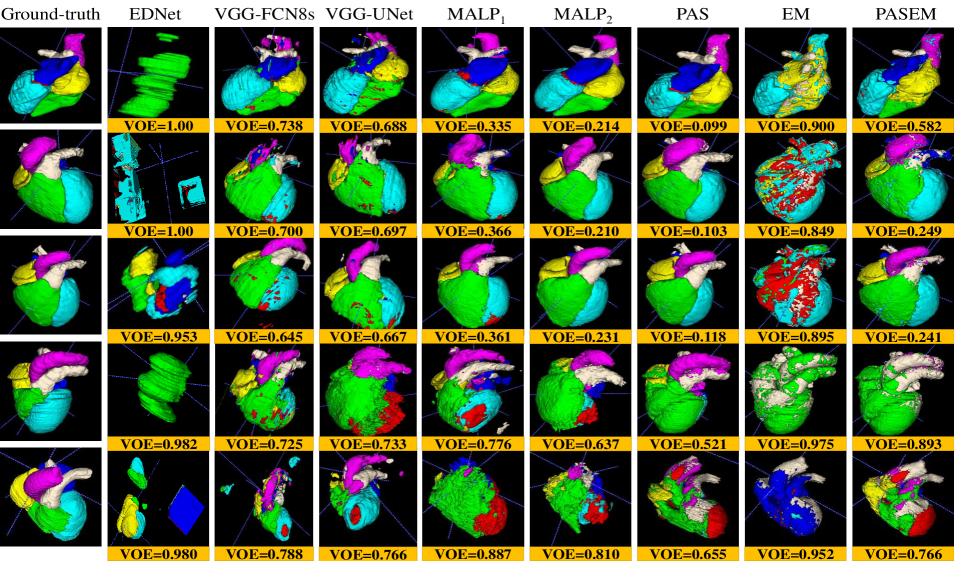

Fig. 7 exhibits the Box and Whisker visualization of all the methods showing the spreads and centers of the DSC, VOE, and Sn metrics for all the 20 test images, either CT or MRI scans.

Fig. 8 (a) and Fig. 8 (b) display the qualitative segmentation results for both the CT (top) and MRI (bottom), respectively, from all the methods.

The experimental results in Table III quantitatively demonstrate that the EDNet is the worst-performing method than the other two CNN-based methods, such as VGG-UNet and VGG-FCN8s, by the margins of and for CT scans and and for MRI scans, respectively, concerning the mDSC. Those two networks also defeat the EDNet for the other two metrics (mVOE and mSn) with significant margins (see in Table III). Although those three networks have the same number of convolutional and pooling layers in the encoder and decoder, they constructionally vary in skip connection employment (see details in subsection II-C). The results on both the imaging modalities reveal that the appliance of skip connection has outputted better-segmented substructures, as the local information from the shallower layers is utilized to reconstruct output masks through the skip connection (see the results in Table III). Again, it is seen from Fig. 7 that the DSC, VOE, and Sn from the EDNet are sparse for both the CT and MRI scans, with significantly fewer median metrics, which demonstrates that EDNet produces scattered results for each of the testing cases. On the other hand, the upper- and lower-whisker for all three metrics are closer for VGG-FCN8s and VGG-UNet than the EDNet (see in Fig. 7), which shows better-robustness of them comparing the EDNet.

Furthermore, the qualitative results in Fig. 8 depict that both the VGG-UNet and VGG-FCN8s provide better-segmented substructures of both the modalities (CT and MRI) than the EDNet. In some examples of the EDNet, none of the target substructures are segmented, which provide VOE as (see upper-whisker in Fig. 7 (b)). The encoders in all three networks have 13-convolutional and 5-pooling layers, where the in-depth features obtained from them have lost spatial location information due to pooling in the encoders. Hence, the output masks from EDNet have less local information, which is solved in the VGG-UNet and VGG-FCN8s due to the concatenation of local information through the skip connection, providing an alternative path for the gradient with backpropagation. It is experimentally validated in our investigations that the additional skipping paths are beneficial for improving the segmentation results of different heart substructures.

III-A2 Results for MALP-based methods

The label propagated segmentation results utilizing different deformed atlas images are quantitatively and qualitatively manifested in Table III, Fig. 7, and Fig. 8. The median and MVF schemes of level propagation, as described in subsection II-B2, generate the heart segmentation results with the mVOEs of and , respectively, for CT scans and and , respectively, for MRI scans. Table III demonstrates that the MVF scheme outperforms the median method of MALP by the margins of and respectively for CT and MRI modalities for mDSC. The former MALP method also outperforms the latter MALP method with significant margins concerning the other two metrics (mVOE and mSn). The Box and Whisker visualization of all three metrics in Fig. 7 for both the methods demonstrate the superiority of the MVF scheme than the median strategy for both the imaging modalities. Fig. 8 (top) and Fig. 8 (bottom) exhibit the qualitative results respectively for CT and MRI scans for both the median (MALP1) and MVF (MALP2) schemes. Those results qualitatively confirm that the segmented substructures from MALP1 suffer from the outliers (see in fifth and sixth columns of Fig. 8), where most of the organs are erroneously labeled with other organs. All the experimental results reveal that the MVF scheme has better dealt with the outliers as it counts the majority of the labels from the voting candidates, whereas the median method estimates the median values of the counter, which may not be matched by the majority voters.

III-A3 Results for probabilistic atlas-based methods

The WHS results of the probabilistic atlas are exhibited in Table III, Fig. 7, and Fig. 8, where we employ our three methods, such as PAS, EM, and PAS+EM (see details in subsection II-B2). The PAS, EM, and PAS+EM schemes of probabilistic atlas provide the heart segmentation results with the mVOEs of , , and , respectively, for CT scans and , , and , respectively, for MRI scans. Table III exhibit that the PAS scheme exceeds the other two methods, such as EM and PAS+EM, by the margins of and for CT scans concerning the mDSC, respectively, whereas it also beats them by the margins of and for MRI scans, respectively, in terms of the mDSC. Similarly, the EM and EM+PAS are also defeated by the proposed PAS method for mVOE and mSn for both the chest imaging modalities with considerable margins (see in Table III). The spreads and centers of the DSC, VOE, and Sn metrics for all the 20 test images (either CT or MRI scans), as exhibited in Fig. 7, also reveal the supremacy of the proposed PAS method over the other two methods (EM and EM+PAS).

However, incorporating the PAS algorithm with an EM algorithm extends the WHS outcomes by the margins of and in terms of mDSC respectively for CT and MRI modalities. Still, the PAS technique is a defeating method. Again, Fig. 8 (top) and Fig. 8 (bottom) show the qualitative WHS outcomes for the CT and MRI scans for the PAS, EM, and PAS+EM designs, respectively. Those results show that the segmented substructures from EM and PAS+EM yield the outliers substructures (see in eight and ninth columns of Fig. 8), where the EM results suffer severely by the outliers. The embodiment of PAS with the EM has significantly reduced the outlier effect from the WHS results of the EM technique, as qualitatively depicted in Fig. 8.